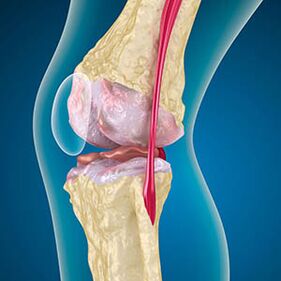

Knee joint arthritis combines two processes: the destruction of the cartilage and the growth of osteophytes or bone spurs.The process stage is determined by radiography.It is believed that arthritis is the destruction of knee joints with age, the natural process of aging.The causes are muscle weakening and poor blood supply to the tissue.How to treat yourself without surgery?Eliminate factors that reduce muscle tone.

With arthrosis, the cartilage of the bone ends is eroded or completely absent.Damaged tissue is not a source of pain because there are no receptors.Inflammation in nearby structures causes characteristic symptoms.

The body continues to regenerate damaged tissue, but the cartilage grows unevenly.As a result, irregularities are formed that damage other elements of the Union.The nature of osteophytes is explained by compensation for a smooth joint cartilage.Another version shows that the growth of "spurs"It is accompanied by an attempt to stabilize the medially or side joint due to muscle weakening.